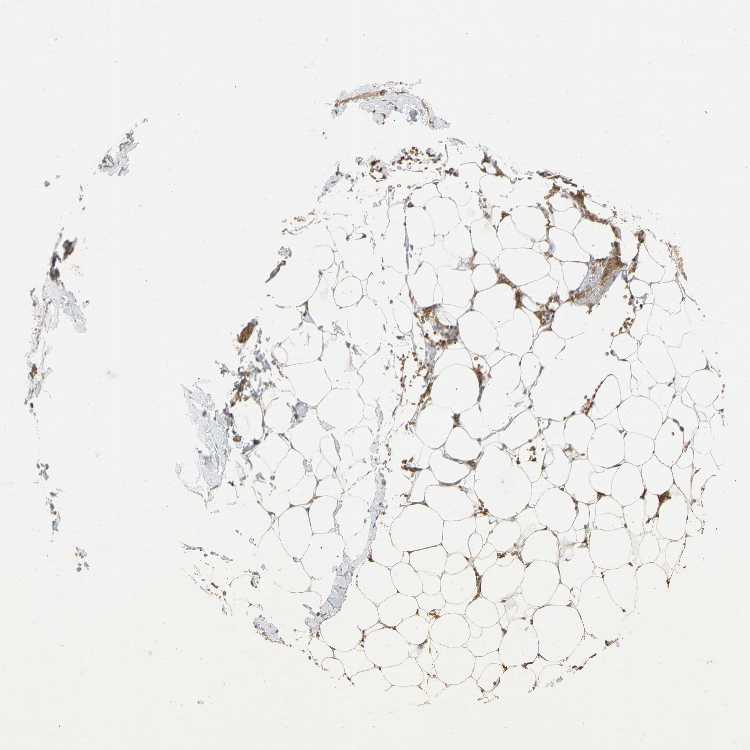

SOFT TISSUE 1 - Antibody stainingi

Antibody staining in the annotated cell types in the current human tissue is reported as not detected, low, medium, or high, based on conventional immunohistochemistry profiling in selected tissues. This score is based on the combination of the staining intensity and fraction of stained cells.

Each image is clickable and will lead to virtual microscopy that enables deeper exploration of all samples and also displays staining intensity scores, fraction scores and subcellular localization as well as patient and tissue information for each sample.

Antibody HPA005681

Fibroblasts Low

Peripheral nerve Not detected

SOFT TISSUE 2 - Antibody stainingi

Fibroblasts Medium